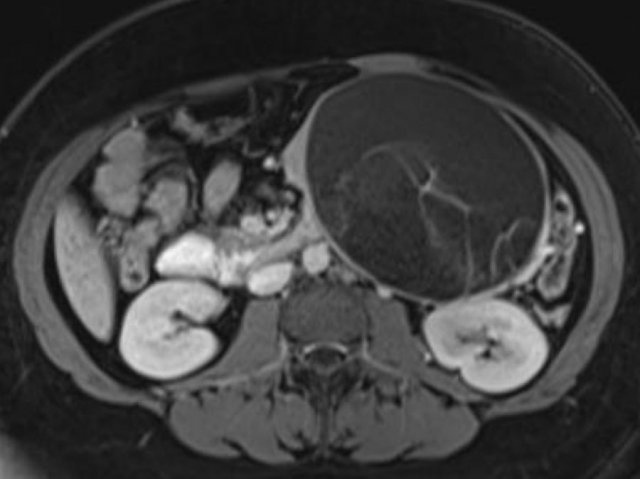

Another example of a serous cystic neoplasm (Fig).

The contrast-enhanced image on the right shows a hypodense lesion with central calcification in the body of the pancreas and subtle enhancement of septations

Notice that on CT it is very difficult to appreciate the cystic nature of these lesions and you might think that you are dealing with a pancreatic adenocarcinoma.

MRI will easily demonstrate the cystic nature of these lesions (fig).

The T2WI with fatsat nicely demonstrates a lobulated hyperintense lesion with central scar, which is characteristic of a SCN.